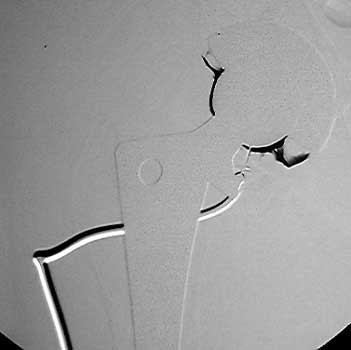

Needle advanced to metal

Aspiration of joint fluid

Aerobic and anaerobic culture tubes

Normal arthrogram